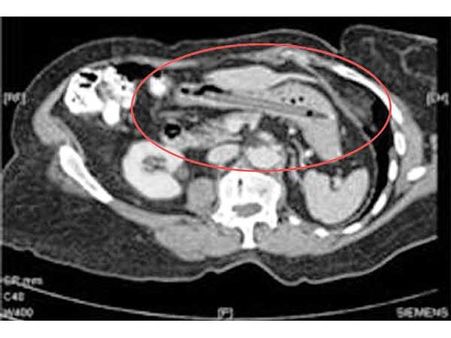

Hand Grenade

Wonder what did this terrorist even think of while placing the hand grenade in his abdomen. Apparently, he was not a good thinker, as he had no means of access to defuse the bomb!